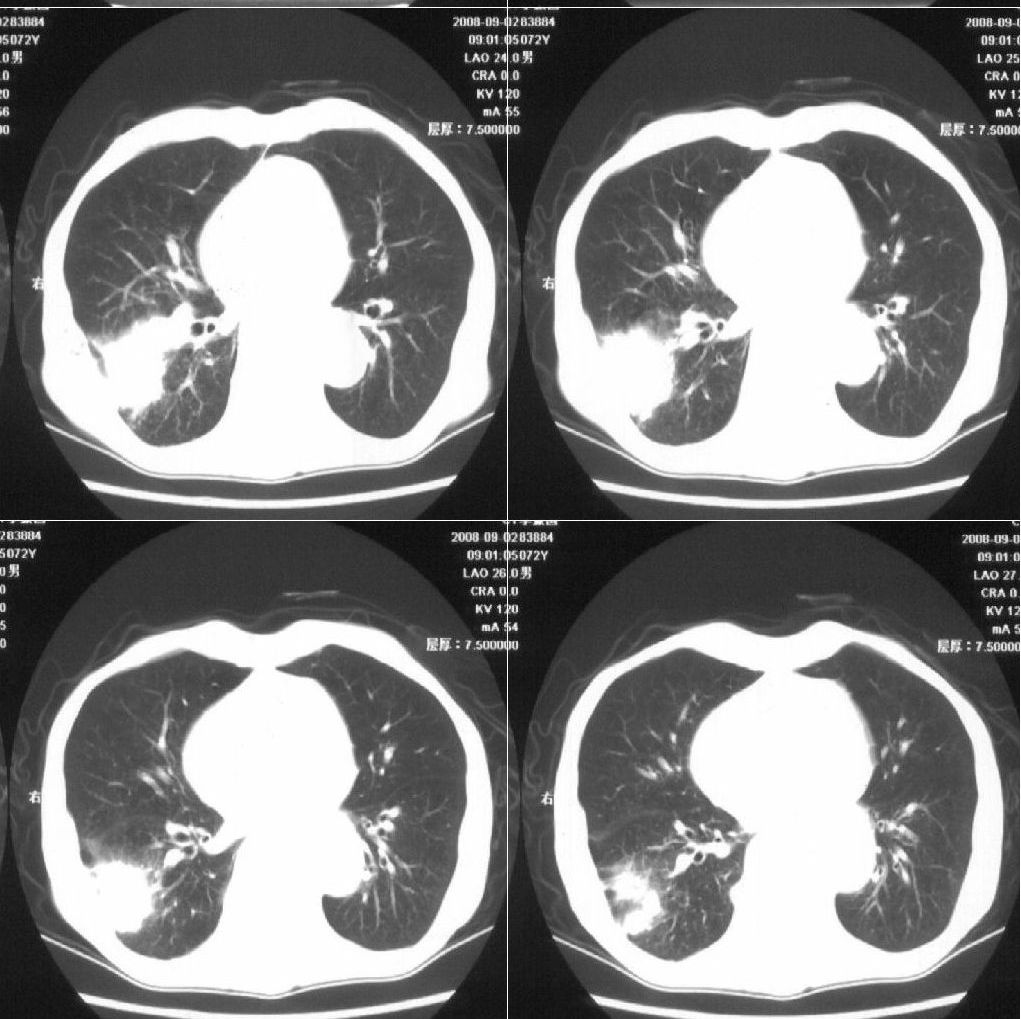

标题: CT15789:男性,72岁。食管癌术后14年。 [打印本页]

标题: CT15789:男性,72岁。食管癌术后14年。

痰培养:见葡萄球菌,霉菌少量生长。(此片系外院所作,仅提供了增强后的ct值为100hu,中心的坏死部分无强化,患者现在身体状况欠佳,为恶液质状态)

考虑右肺下叶感染性病变(肺脓肿?);建议抗炎治疗后复查。

该患者通过抗炎治疗明显好转:当时患者消瘦,实是因为患者进食量不多。患者有食道癌,因发生原发肺癌的机率并不高,当时的ct片除了增强感觉有强化外(其实这信息也并不确定,因为是外院ct),其实并没有发现支气管腔改变等直接征象。经过治疗,患者现在一般情况良好。以下是9月22日的复查片,发现病灶吸收明显。纵隔窗就不上传了。